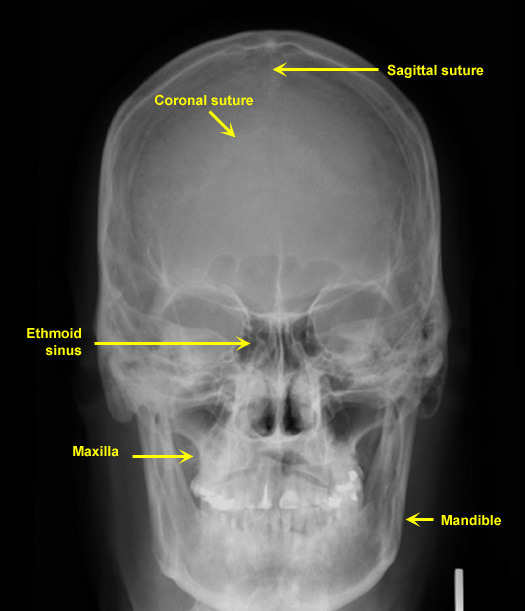

Plain Films of Skull and Spine